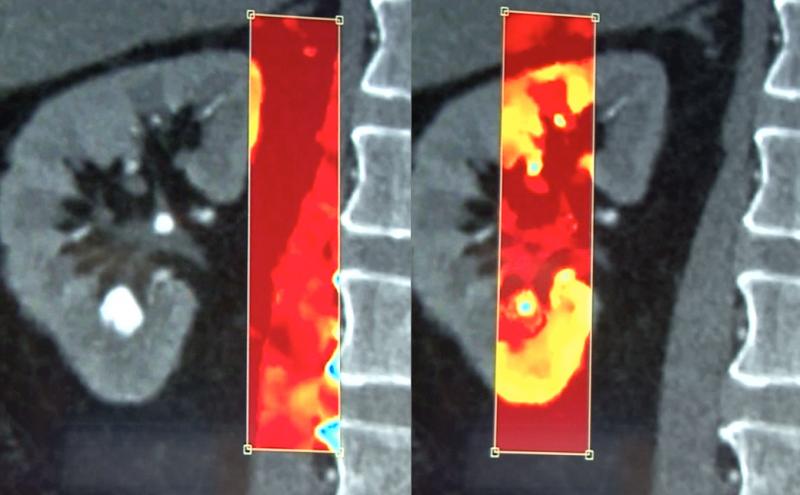

IQon allows use of a spectral window that can be moved around the image to show the chemical makeup of tissue in the frame. Here it shows the composition of a kidney stone with regular CT imaging and spectral.

The spectral CT is on all the time, so nothing needs to change in the clinical workflow. The spectral data can be accessed after a scan to help differentiate materials such as metal and bone to help reduce beam hardening. Spectral data can also help differentiate calcified arterial plaque or kidney stones based on the chemical composition of materials. It can also reconstruct a virtual non-contrast CT scan from contrast enhanced images by filtering out the iodine based on the spectral data.